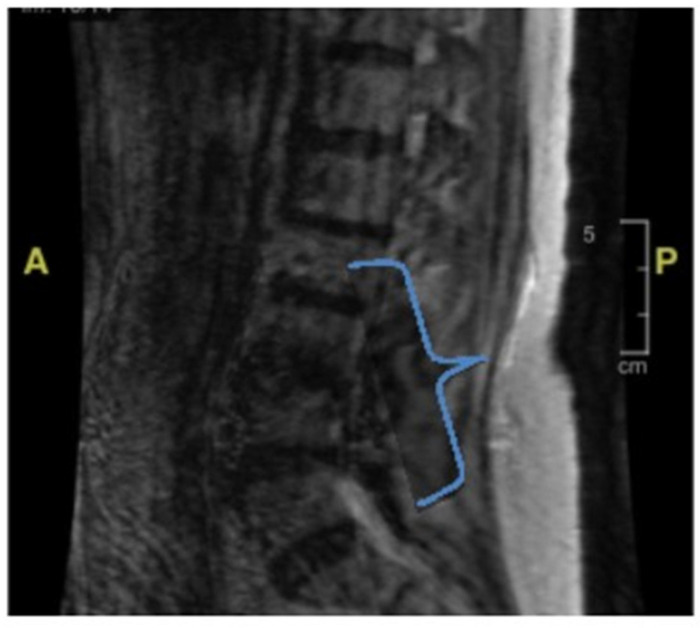

Background/Objectives: Lower-extremity weakness in older adults is often overlooked, yet it can have reversible or medical causes that contribute to increased falls. Common factors include vision disturbances, impaired balance due to otolith dysfunction, arthritis-related immobility, and lower-extremity neuropathy. This case presents a unique diagnostic challenge in evaluating bilateral lower-extremity weakness and recurrent falls in an older adult, highlighting the complexity of diagnosing conditions with overlapping symptoms. Case Presentation: The patient, a woman with a history of a neuroendocrine tumor, experienced progressive weakness in her lower extremities, along with oculomotor and facial muscle involvement, despite extensive testing. Key clinical findings included elevated protein levels in cerebrospinal fluid, suggesting the possibility of an infectious or autoimmune process. A thorough investigation was conducted, including testing for both common and rare conditions such as Guillain-Barré syndrome, Lyme disease, and tuberculosis. Results: Despite comprehensive diagnostic efforts, no clear etiology was identified. The patient's condition was eventually considered to be related to carcinomatosis meningoencephalitis, a rare complication from a previous cancer diagnosis. Given the progressive nature of her symptoms and lack of treatment options, she was transitioned to palliative care. Conclusions: This case highlights the importance of a comprehensive differential diagnosis in older patients with unexplained weakness and falls. Rare neurological conditions should not be overlooked, even when more common causes are suspected. Clinicians should remain aware that falls and weakness in older adults may stem from various pathologies, some of which are reversible if identified early, and rare causes must always be considered when standard treatments fail.